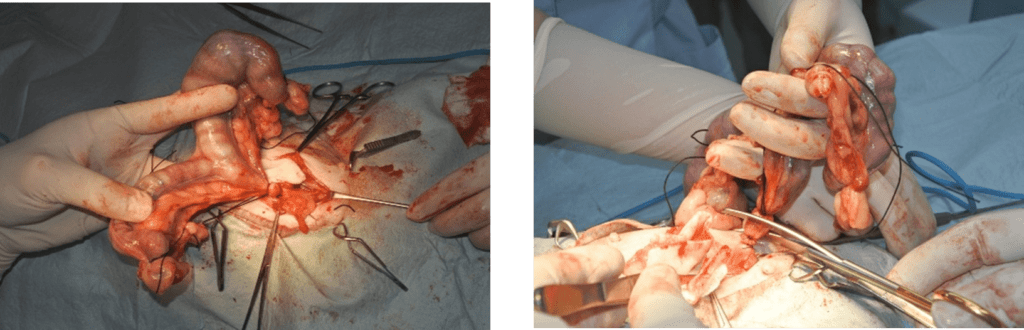

お腹の中から、膿でパンパンに膨れ上がった子宮と、それに繋がる卵巣を探し出します。子宮は非常に脆くなっており、破裂しやすいため、細心の注意を払って扱います。卵巣と子宮に繋がる血管を、それぞれ特殊な糸で一本一本しっかりと結びます。これを出血しないように確実に行うことが、手術の最も重要なポイントの一つです。

血管の処理が終わったら、膿が溜まった子宮と卵巣を体の中から丸ごと取り出します。この時、膿がお腹の中に漏れ出さないよう、非常に慎重に操作します。子宮を摘出した後、お腹の中に膿が漏れていないか、異常な出血がないかなどを最終確認します。必要に応じて、お腹の中を温かい生理食塩水できれいに洗浄します。

手術で摘出した子宮は、切開した瞬間に膿が噴き出すほど重度に腫れ上がっていました。